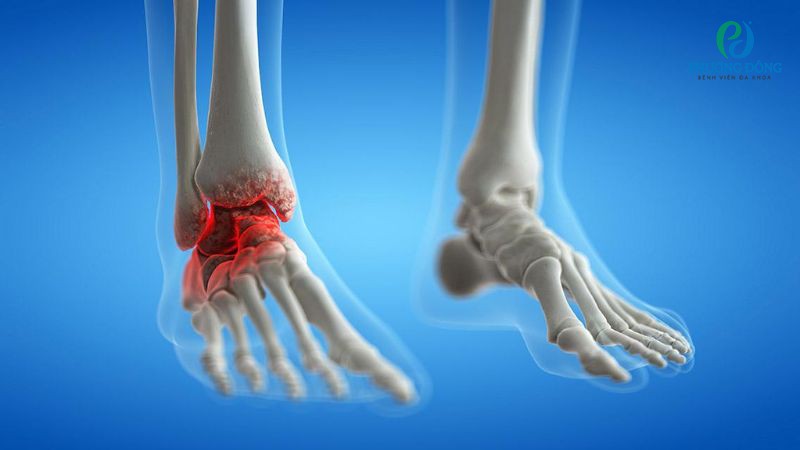

Sưng khớp cổ chân không phải bệnh lý, đây có thể là triệu chứng của viêm khớp cổ chân, khiến mô mềm quanh khu vực cổ chân bị phù nề. Người bệnh có thể xuất hiện kèm theo tình trạng đau nhức, khả năng vận động bị hạn chế, cứng khớp, dính khớp dẫn đến mất khả năng vận động.

Sưng khớp cổ chân là triệu chứng của nhiều bệnh lý cơ xương khớp

Trong một số trường hợp, sưng khớp còn cảnh báo các bệnh lý xương khớp khác như viêm khớp dạng thấp, thoái hóa khớp. Bệnh nhân khi thấy khó chịu, đau nhức, giới hạn phạm vi chuyển động cần nhanh chóng đến bệnh viện thăm khám, tìm nguyên nhân.